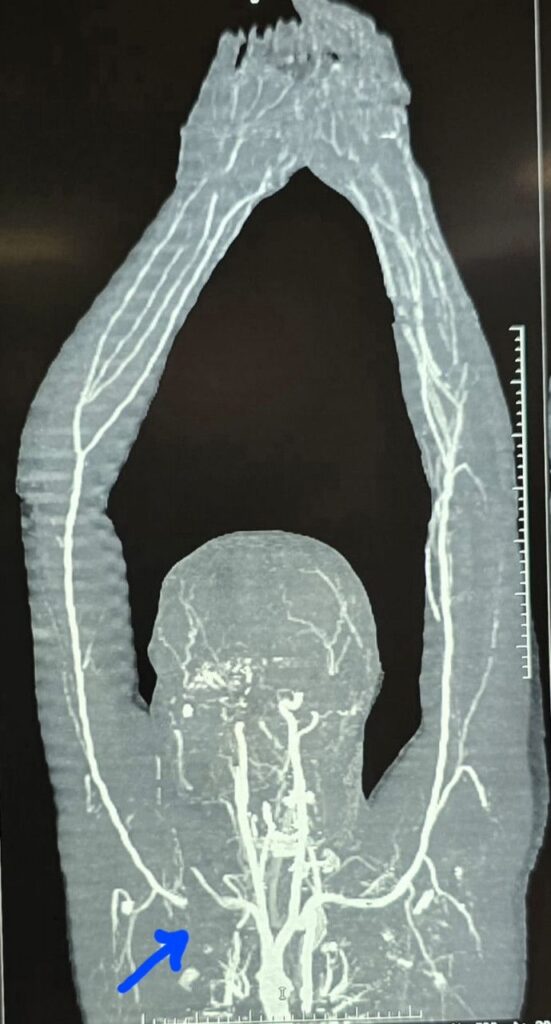

इस केस की विस्तृत जानकारी देते हुए विभागाध्यक्ष (हार्ट- चेस्ट और वैस्कुलर सर्जरी) डॉ. कृष्णकांत साहू ने बताया कि :- अम्बेडकर अस्पताल के ट्रॉमा यूनिट में 34 वर्षीय एक मरीज अत्यधिक रक्तस्राव और मरणासन्न अवस्था में लाया गया। मरीज इलेक्ट्रिक व्हीकल कंपनी में काम करता है और अमलेश्वर का निवासी है। परिजनों के अनुसार, मरीज अपने परिवार के साथ मोटरसाइकिल से रायपुर रेलवे स्टेशन की ओर जा रहा था, तभी इलेक्ट्रिक रिक्शा से टक्कर हो गई। विवाद के दौरान रिक्शा चालक ने मरीज के बाएं कंधे पर धारदार चाकू से हमला कर दिया। घाव इतना गहरा था कि कंधे की हड्डी (क्लेविकल बोन) के पीछे से गुजरने वाली मुख्य धमनी सबक्लेवियन आर्टरी पूरी तरह क्षतिग्रस्त हो गई।

सबक्लेवियन आर्टरी की सर्जरी विशेष रूप से उसके दूसरे भाग (सेकंड पार्ट) में बेहद चुनौतीपूर्ण होती है, क्योंकि यह धमनी छाती के भीतर कॉलर बोन के पीछे स्थित रहती है। पट्टी हटाते ही अत्यधिक रक्तस्राव की आशंका बनी हुई थी, जिसके लिए वैस्कुलर कंट्रोल अत्यंत आवश्यक था। स्थिति की गंभीरता को देखते हुए निर्णय लिया गया कि मरीज की कॉलर बोन को काटकर धमनी तक पहुंच बनाई जाए।

कॉलर बोन को काटने के बाद पाया गया कि धमनी लगभग 3 सेमी तक पूरी तरह क्षत-विक्षत हो चुकी थी। इसे जोड़ने के लिए 7×30 मिमी. साइज का डेक्रॉन ग्राफ्ट (कृत्रिम नस) लगाया गया। सर्जरी के दौरान लगभग 5 यूनिट रक्त चढ़ाया गया और करीब 4 घंटे की कड़ी मशक्कत के बाद हाथ में पुनः रक्त प्रवाह शुरू हो सका। इस दौरान ब्रैकियल प्लेक्सस (तंत्रिका तंत्र) को पूरी तरह सुरक्षित रखा गया, क्योंकि इसमें क्षति होने पर हाथ में स्थायी लकवे की संभावना रहती है। ऑपरेशन के बाद कॉलर बोन को प्लेट लगाकर वापस जोड़ दिया गया